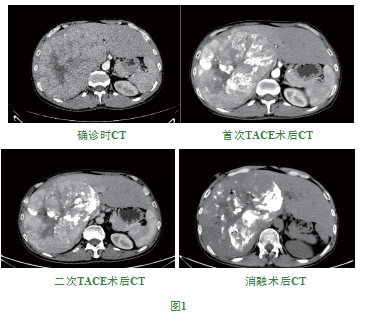

患者男,40岁,因上腹部不适,于2019年4月19日我院行胸部及上腹部平扫+增强示:肝右叶巨块肝癌可能大。AFP小于5ng/mL,患者长期饮酒史且无乙肝或丙肝病史,综合考虑患者为酒精性肝癌。因肿瘤较大,肝功能较差,无法手术切除,但左肝未发现明显病灶,可通过栓塞肝右动脉,致使左肝代偿性增大。遂于2019年4月29日、2019年5月29日、2019年8月05日给予TACE术,2019年8月16日行CT引导下单针多点消融术。左叶最大径线变化如下:205mm(2019年4月19日)、211mm(2019年5月27日)、215mm(2019年8月2日)、216mm(2019年8月16日);各转氨酶逐步下降:首次TACE术后ALT由61 U/L降低至51 U/L,AST由49 U/L降至45U/L,患者行消融术后第二天复查肝功良好(ALT:69 U/L,AST:71 U/L),数值略高系消融术致肝组织损伤相关。术后患者一般情况可,术后一个月复查,肿瘤体积减小,增强检查未见明显复发及转移征象。

本例患者系酒精性巨块型肝癌,瘤体局限于肝右叶,但瘤块体积较大(19.1×19.5×11.9cm),患者首诊时白蛋白低于30g/L,ALT与AST指标较高,无法进行根治性手术治疗,首选全身治疗联合局部控制。根据目前研究[10]及NCCN指南乐伐替尼、索拉非尼可用于晚期肝细胞肝癌的一线治疗,而PD1/L1抑制剂在治疗晚期肝细胞肝癌取得显著临床效果,可用于肝癌二线治疗。但本例患者合并原发性甲状腺功能低下、凝血功能较差,暂不适宜靶药或免疫治疗,TACE联合MWA局部治疗更利于患者治疗。经三次TACE术后,肿瘤体积缩小,碘油沉积效果好,肝左叶逐步明显代偿增大,但患者转氨酶略高于正常,白蛋白稳定与28~33之间且PT-SEC位于16~18秒之间,为避免化疗药物加重患者肝脏负担出现不良后果,顾联合CT引导下单针多点微波消融术,多点交叉消融,进一步破坏瘤体组织,避免转移和复发,进一步控制肿瘤。术中未出现严重不良反应。术后患者发热(<39℃),考虑肿瘤坏死性热,经对症退热治疗后,一周后体温下降。患者肝硬化、凝血功能差,为避免术中及术后严重出血,术中避免穿刺大血管,烧灼穿刺针道,术前、术后给与患者保肝、注射维生素K1等治疗,密切关注凝血时间,使其低于16秒。术后一个月复查,可见肿瘤体积缩小,未见复发征象,患者白蛋白明显增高(>30g/L),基本情况良好。